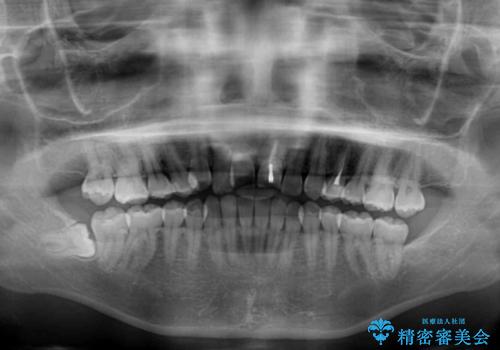

前歯の反対咬合 非抜歯のワイヤー矯正

- 前歯のでこぼこを気にして来院された患者様です。

1年半はかかると思っていた治療期間ですが、反対咬合となっている前歯が思いの外早く動き、僅か9ヶ月で終了させることができました。